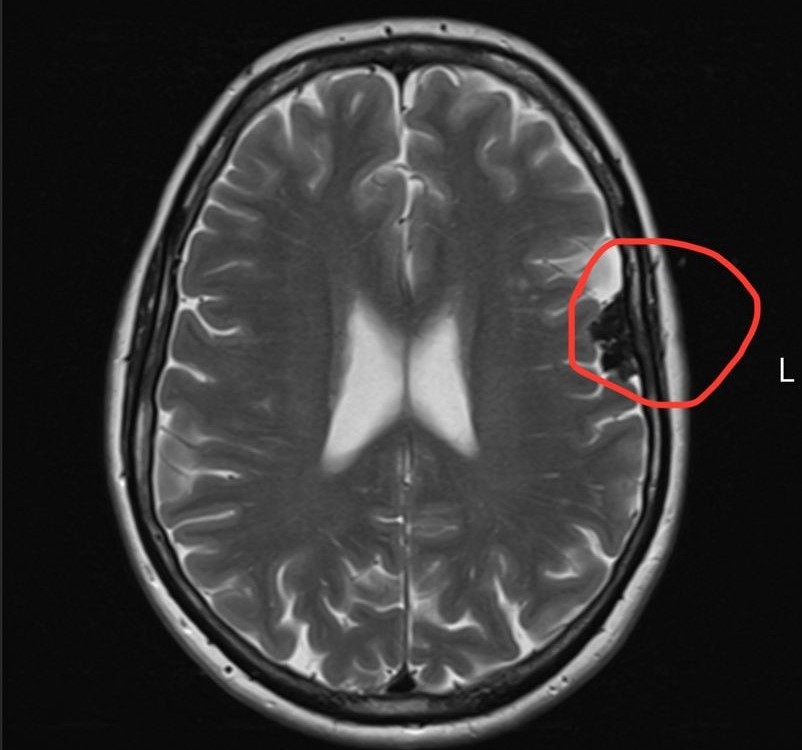

An MRI later revealed a meningioma, a type of brain tumour.

“Then, when I finally saw the specialist, they told me not only did I have one tumour, but actually two.”

Doctors advised Elizabeth to “watch and wait” since both tumours were benign and slow-growing.

For now, she’s undergoing regular MRI scans to monitor their growth.